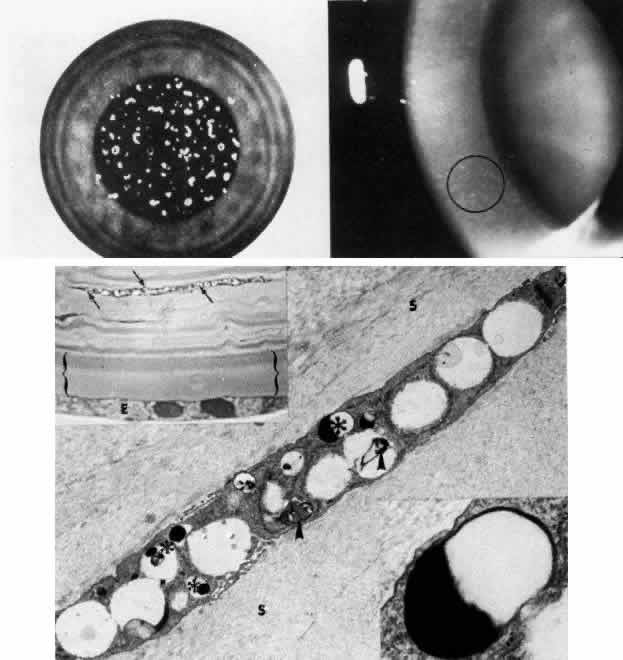

In sclerocornea (Fig. 4), the limbus is ill-defined since opaque scleral tissue with fine vascular conjunctival arcades extends into the peripheral cornea. A broad range of corneal involvement is possible, with the most extreme being complete sclerification of the cornea. Ninety percent of cases are bilateral, although generally asymmetric. Most cases are sporadic; there is no known heredity. Sclerocornea is nonprogressive and must be differentiated from interstitial inflammatory conditions and arcus juvenilis (congenital peripheral lipid deposition, also known as anterior embryotoxon). Sclerocornea is associated with cornea plana in approximately 80% of cases.44 Other associated ocular abnormalities include microphthalmos, iridocorneal synechiae, persistent pupillary membrane, dysgenesis of angle and iris, congenital glaucoma, colobomas, and posterior embryotoxon of the fellow eye.45 Somatic abnormalities sometimes occur along with associated chromosomal abnormalities; they include mental retardation, deafness, and craniofacial, digital and skin abnormalities.44

Fig. 4. Sclerocornea. Schematic drawing of ocular features Top left. In a minimally affected patient with additional findings of ptosis, strabismus, and hearing loss, only the peripheral cornea is opacified. Top center. In this advanced case with chromosomal translocation and multiple congenital abnormalities, the entire cornea is sclerified and the fine vascular arcades extend centrally from the conjunctiva and sclera. Top right. Light micrograph of anterior cornea shows edematous disorganization of epithelium, fragmentation of Bowman's membrane (B), and interstitial vascularization (V) (hematoxylin-eosin, × 200). Middle left. Transmission electron micrograph of normal human corneal stroma is shown for comparative purposes. Note uniform 240- to 260-nm collagen fibril diameter (× 50,000). Middle right. Transmission electron micrograph of sclerocornea at same magnification shows disorganized array of collagen fibrils that measure as much as three times normal diameter (× 50,000). Bottom. Transmission electron micrograph of posterior cornea shows abnormal Descemet's membrane of less than 1μm thickness (DM, bracketed) and attenuated endothelial cells (× 10,500). (Schematic. Grayson M: Diseases of the Cornea, p 32. St. Louis, CV Mosby, 1979; Top center and right. Rodrigues MM, Calhoun J, Weinreb S: Sclerocornea with an unbalanced translocation [17p, 10q]. Am J Ophthalmol 78:49, 1974)

Ultrastructural studies22,46,47 have shown the involved stroma to assume the morphologic features of scleral tissue, with irregularly arranged collagen fibrils of variable and immensely enlarged diameter for corneal tissue (up to 150 nm, comparable to normal scleral collagen). The precise lamellar organization of normal corneal stroma is not present; thus optical clarity is not achieved. Various abnormalities of endothelium and Descemet's membrane exist, from attenuation to focal absence. Descemet's membrane is generally thin, with multilaminar deposition of basement membrane-like collagen.

Pathophysiologically, sclerocornea may result from developmental arrest of limbal differentiation during neural crest migration, as occurs with the other mesenchymal dysgeneses.22